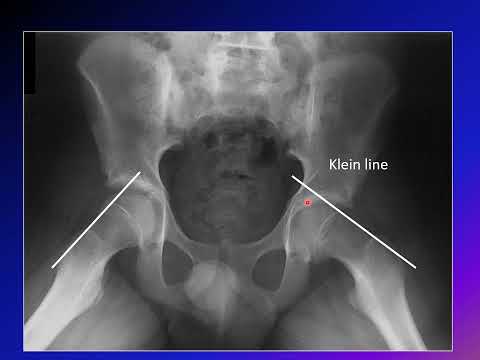

Slipped Capital Femoral Epiphysis (SCFE)

OREF India Web-class for postgraduates – Adolescent Coxa-Vara/ Slipped Capital Femoral Epiphysis

Paediatric Orthopaedic Society of India 9th POSI PG Gurukul: Slipped Capital Femoral Epiphysis

33rd TNOA PG Teaching Program: SLIPPED CAPITAL FEMORAL EPIPHYSIS